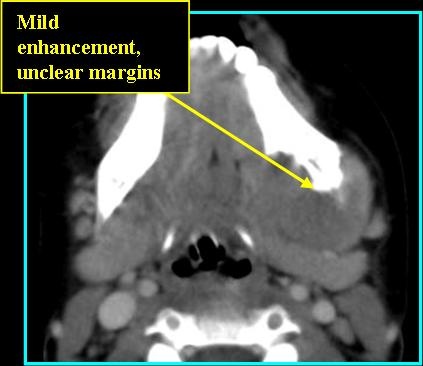

- Often observed as a poorly marginated trans-spatial enhancing mass in the extracranial head and neck

- May be well-defined or invasive - displacing and eroding surrounding bone

Radiologic Findings

- On CT: Mild to moderate enhancement with contrast, may appear malignant, has no observable tumor matrix or calcification/ossification